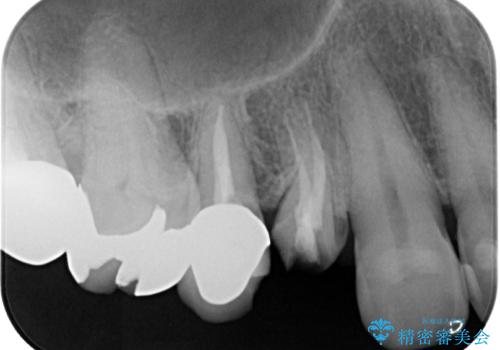

- 「以前治療した歯の被せものが外れてしまった」とのことで、右上の小臼歯の被せもの脱離を主訴に来院されました。

診察の結果、被せもの(クラウン)だけでなく、土台(コア)ごと外れてしまっている状態でした。根管治療済みの歯ではありますが、今回患者様のご希望により、根管治療の再治療は行わず、補綴処置のみを行う方針となりました。

残存歯質の確認と感染リスクのチェック